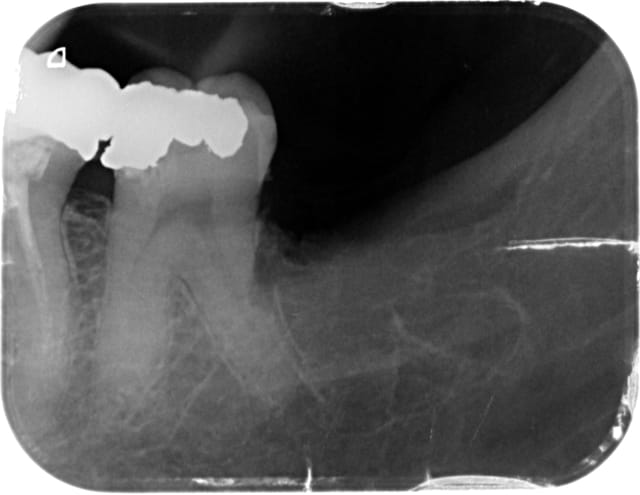

Je fais quoi? Pericoronite sur pericoronite.

Examen radio complementaire avant extraction?

48 op ex uguvk5 - Eugenol

Op ex2 iyntzw - Eugenol

paradoxe

30/07/2013 à 14h12

aterman écrivait:

-----------------

> Je fais quoi? Pericoronite sur pericoronite.

> Examen radio complementaire avant extraction?

Tu envois à mario180 pour lui faire plaisir;-)

Sinon un examen scan ou cone pour pouvoir préciser la position de la dent par rapport au nerf inf en 3D, bien sur.